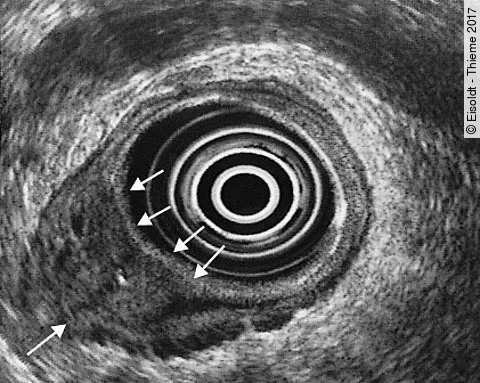

Eisoldt - Thieme 2017

Quiz der Woche25-jähriger Mann mit schmerzlosem Knoten am Hals

Bei einer Routineuntersuchung stellt sein Betriebsarzt bei dem 25-jährigen Mann einen schmerzlosen Knoten im rechten Schilddrüsenlappen fest. Bildgebung und Labor verraten worum es sich handelt  – Wissen Sie die Diagnose?